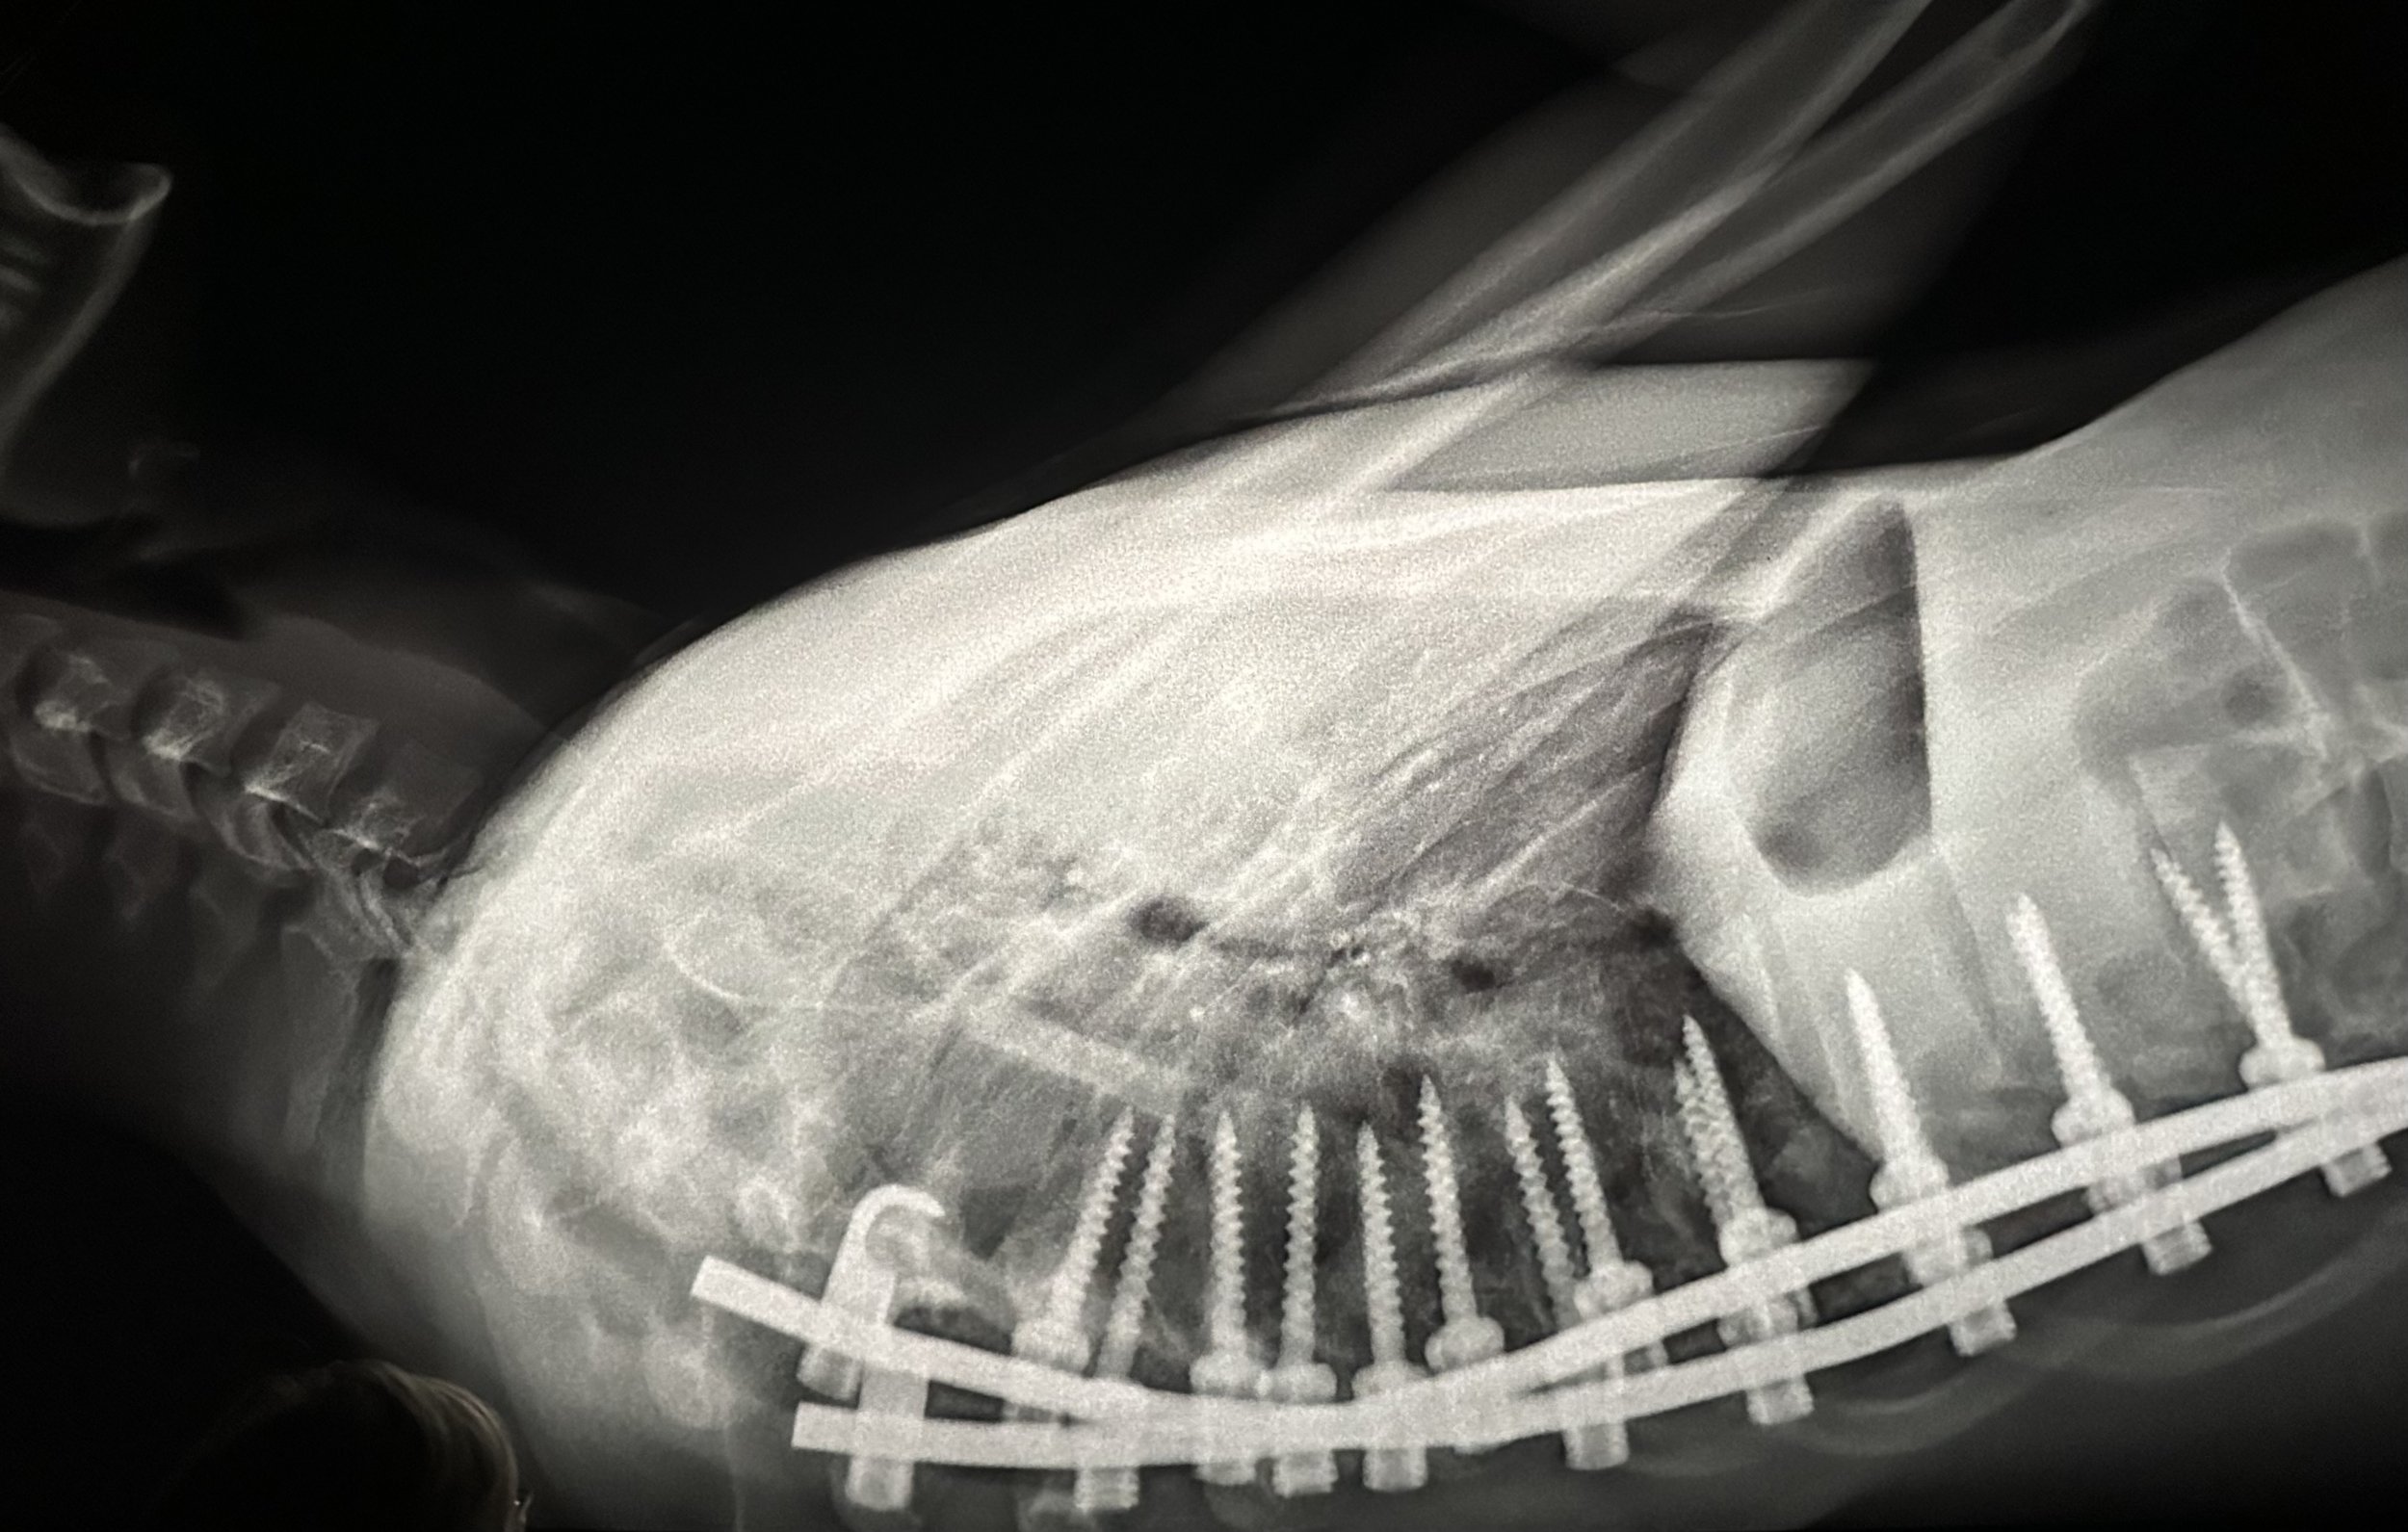

The single shot which is most clearly emblazoned on my memory is the shot of the scalpel cutting open the pregnant woman’s belly for a Cesarean. The doctors pull the opening apart with apparent violence, reaching in to scoop out the baby, who is, thankfully, very small but apparently healthy. The mother indicates that she still has sensation in her belly and feel the pinchers when they touch her, but she makes no sound, so we have no idea what sort of pain she is feeling, or if she is feeling anything at all.